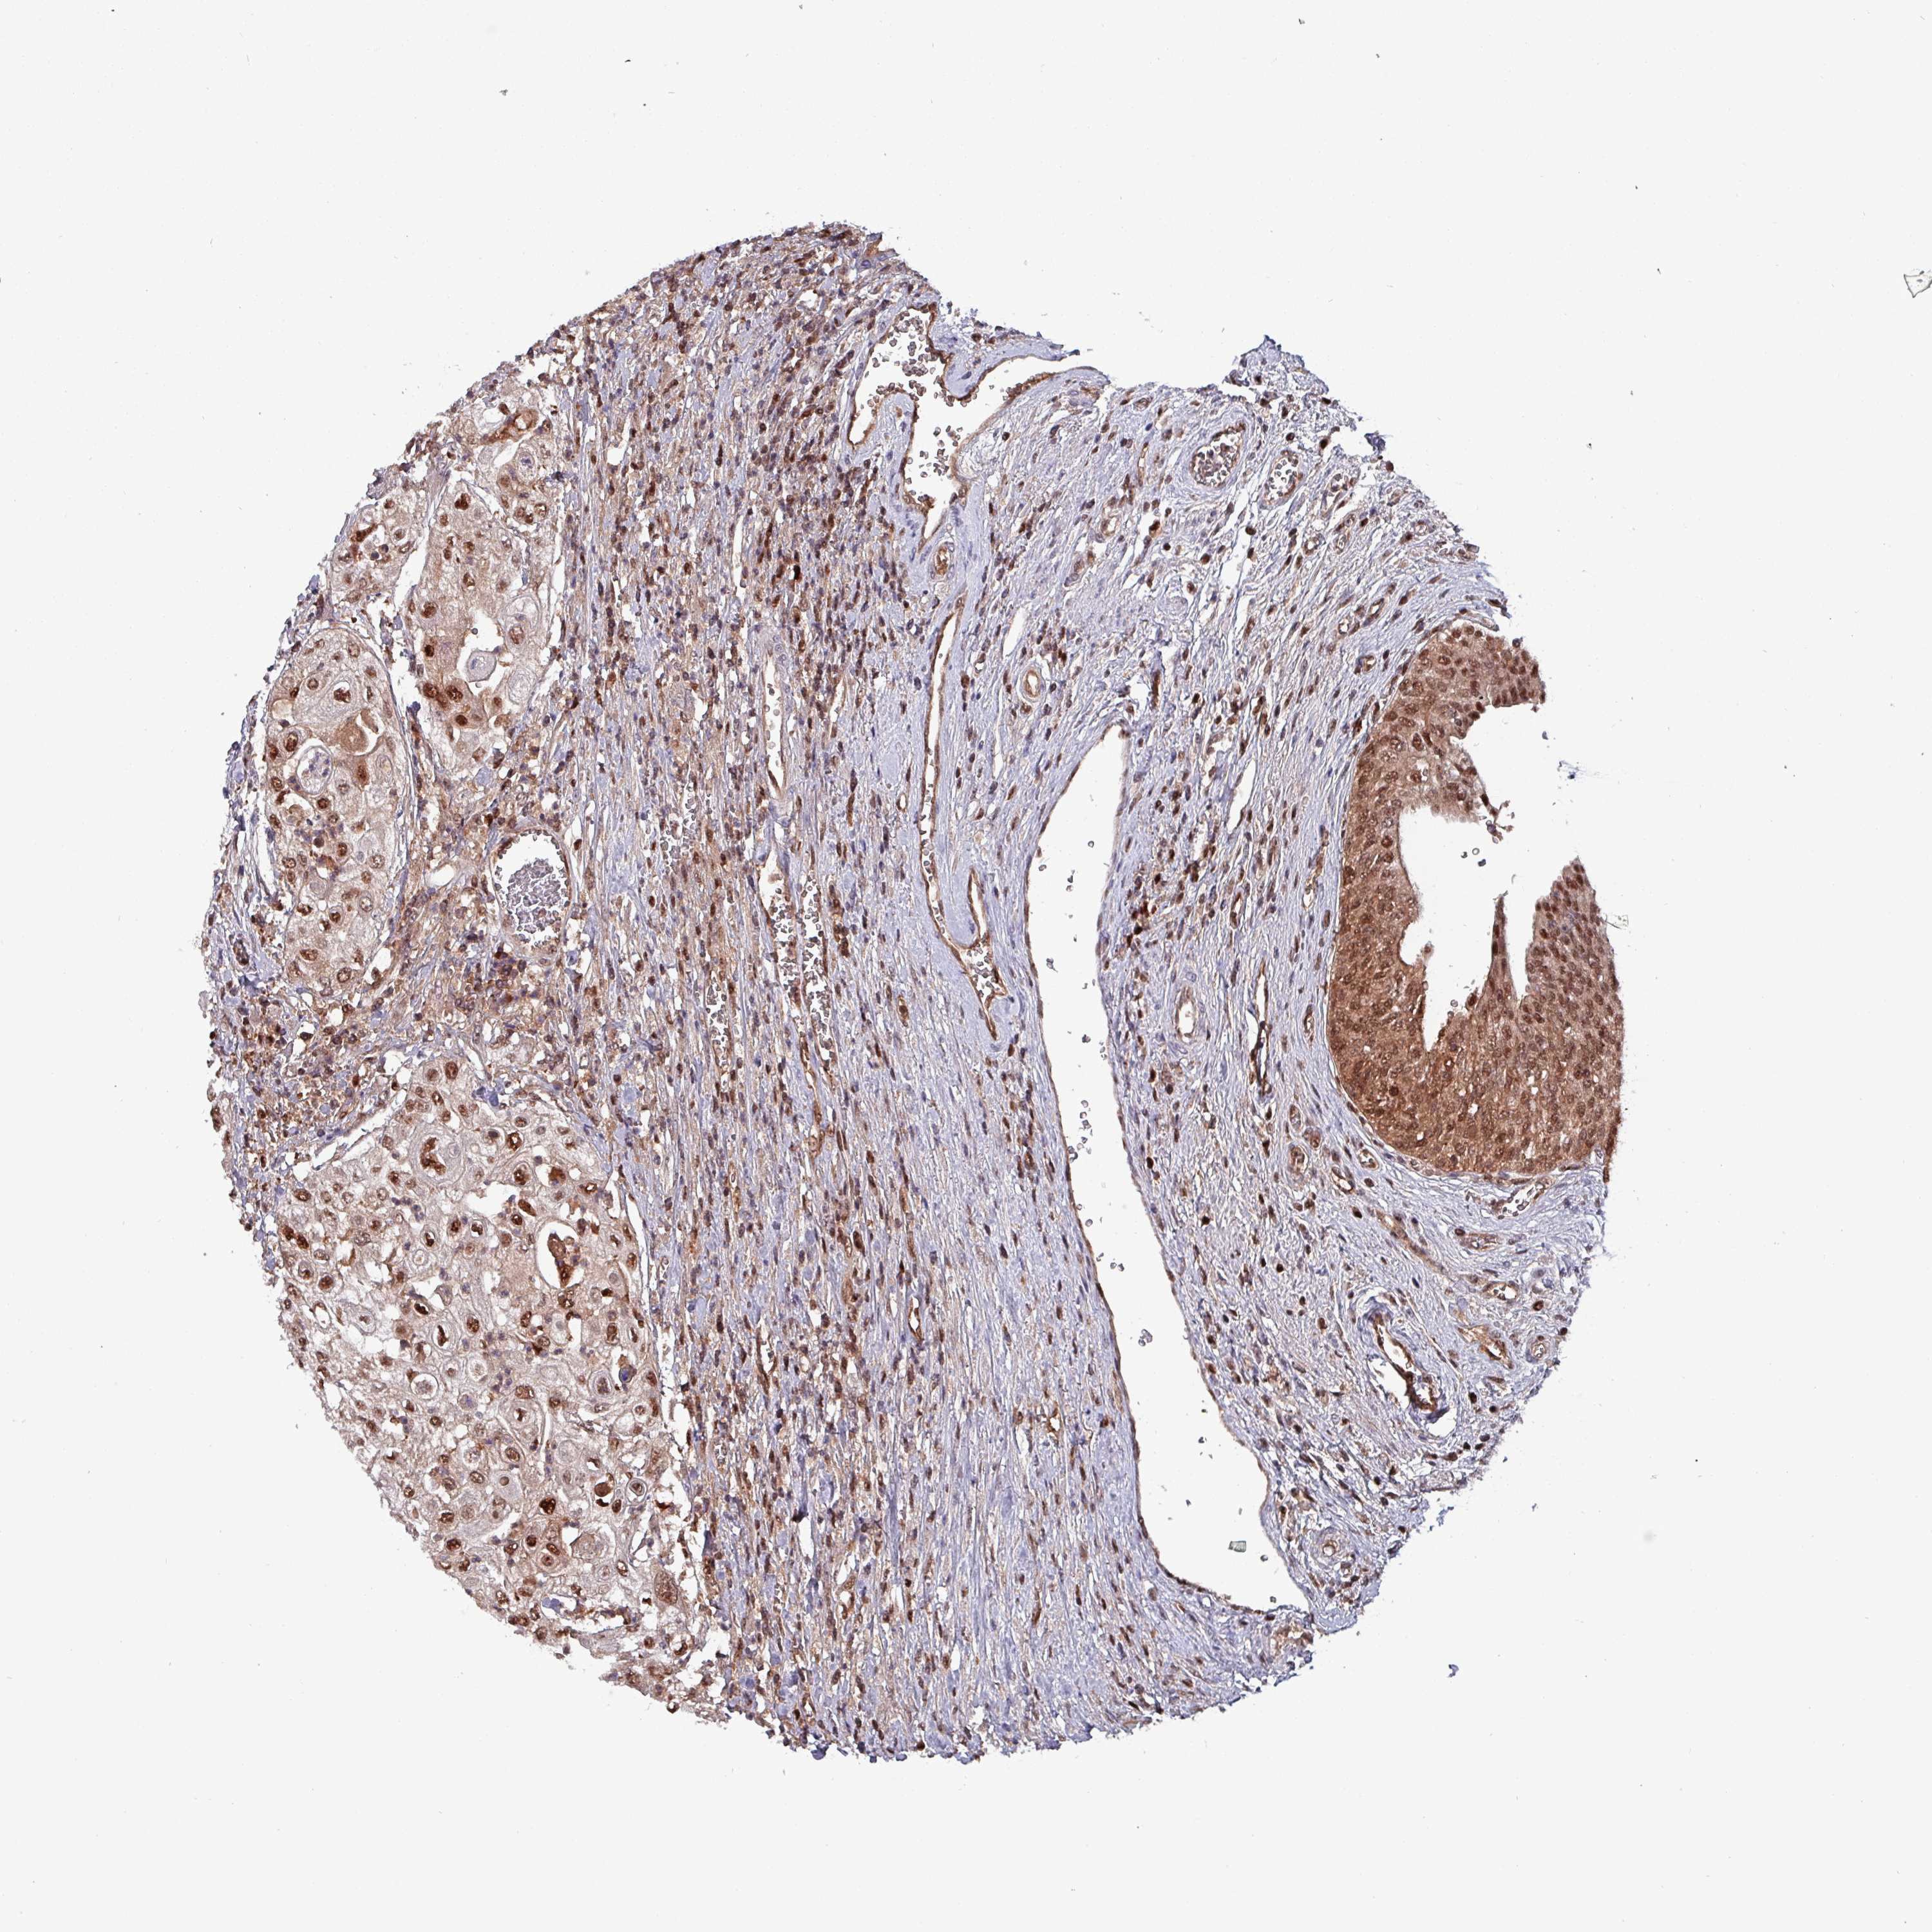

UROTHELIAL CANCER - Protein expressioni

A mouse-over function shows sample information and annotation data. Click on an image to view it in a full screen mode. Samples can be filtered based on level of antibody staining by selecting one or several of the following categories: high, medium, low and not detected. The assay and annotation is described here.

Antibody stainingi

Antibody staining in the annotated cell types in the current human tissue is reported as not detected, low, medium, or high, based on conventional immunohistochemistry profiling in selected tissues. This score is based on the combination of the staining intensity and fraction of stained cells.

Each image is clickable and will lead to virtual microscopy that enables deeper exploration of all samples and also displays staining intensity scores, fraction scores and subcellular localization as well as patient and tissue information for each sample.

Antibody HPA046995

Antibody HPA050327

Urothelial carcinoma, High grade

Urothelial carcinoma, Low grade

Urothelial carcinoma, NOS